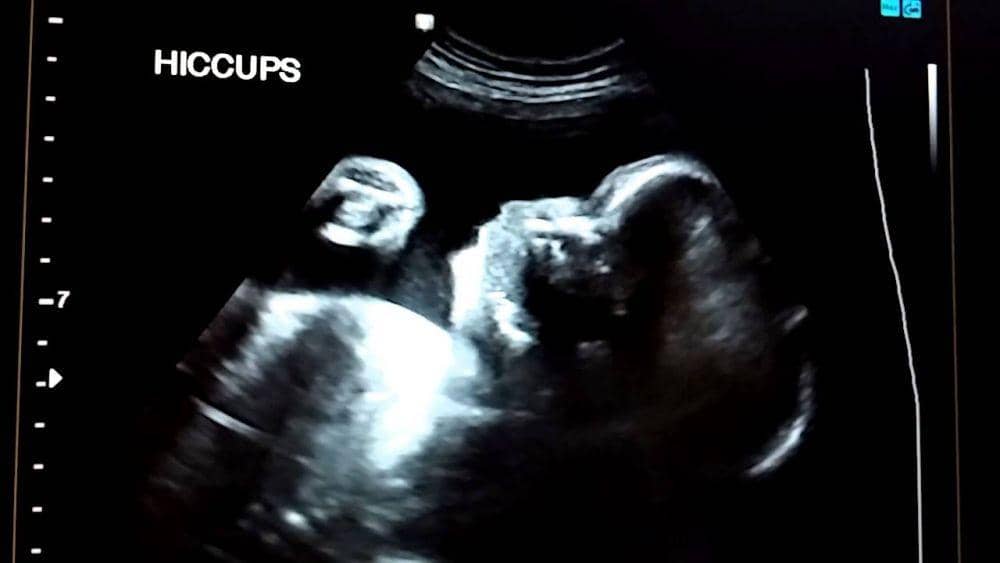

9. Bayi juga bisa cegukan

Cegukan mulai terjadi setelah tiga bulan pertama. Ini tanda bahwa mereka mulai belajar bernapas. Cegukan tersebut akan menyebabkan ibu merasakan tendangan kecil di perutnya.